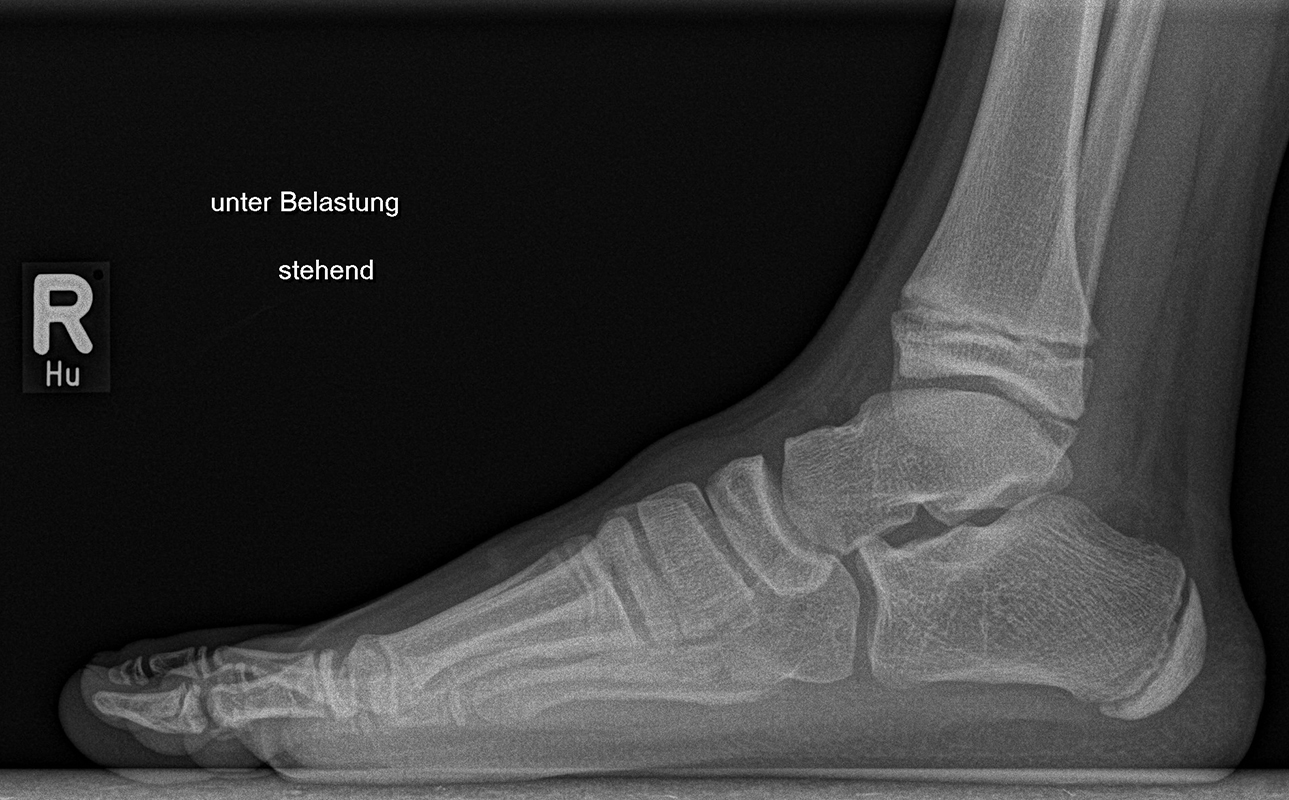

Diagnostisches Vorgehen

Damit die minimalinvasive Fußchirurgie zur Korrektur kindlicher oder jugendlicher Fußdeformitäten erfolgreich angewendet werden kann, erfordert die präoperative Diagnostik Röntgenbilder in drei Ebenen am stehenden Fuß. Röntgenbilder ohne Belastung des Fußes sind nicht zielführend. Im Fall von schweren Rückfußdeformitäten wird das obere Sprunggelenk in die radiologische Diagnostik mit einbezogen in Kombination mit der Rückfußaufnahme unter Belastung („Saltzman View“). Das OSG wird in zwei Ebenen geröntgt. Die streng seitliche Aufnahme des OSG kann bei den komplexen Fußdeformitäten mit der seitlichen Aufnahme des Fußes unter Belastung kombiniert werden. Das reduziert die diagnostische Strahlenbelastung der Kinder.

Indikationen für die beschriebenen Röntgenaufnahmen sind Klumpfußdeformitäten zur Beurteilung eines „flat top talus“ oder neurologische Grunderkrankungen mit varischer Fersenstellung wie zum Beispiel bei HSMN (Hereditäre Sensorische Motorische Neuropathie).